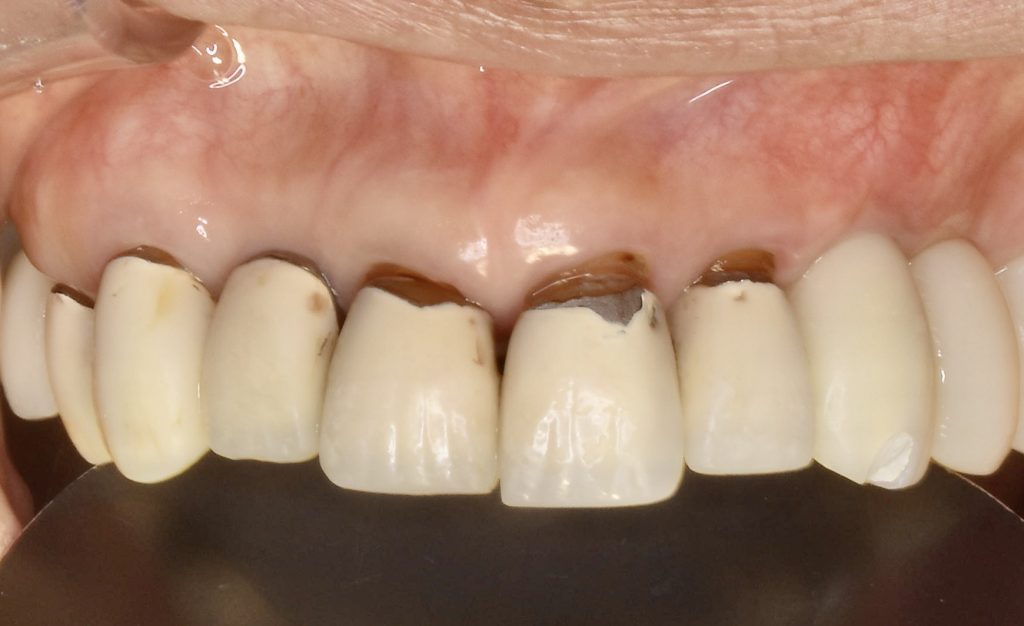

下記の症例は骨幅が薄く、このままでは長期的に安定したインプラント治療が不可能だったので、抜歯と同時に骨造成(GBR)を行い、その後歯肉移植(FGG)を行い、術後安定した経過を辿るよう配慮致しました。